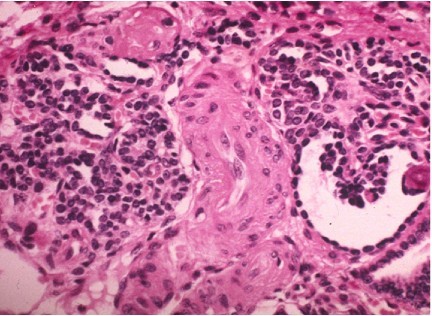

A five year old male is referred for evaluation after his fourth episode of urinary tract infection. Mother received limited antenatal care during pregnancy. Creatinine is normal. Renal ultrasound shows a small echogenic right

kidney with a dilated ureter. Radionucleotide scan shows left kidney contributes 80% of function, right kidney 20%. Based on the kidney biopsy below, what is his diagnosis, prognosis and treatment?

Renal dysplasia

Congenital anomalies of the kidney and urinary tract (CAKUT) due to: